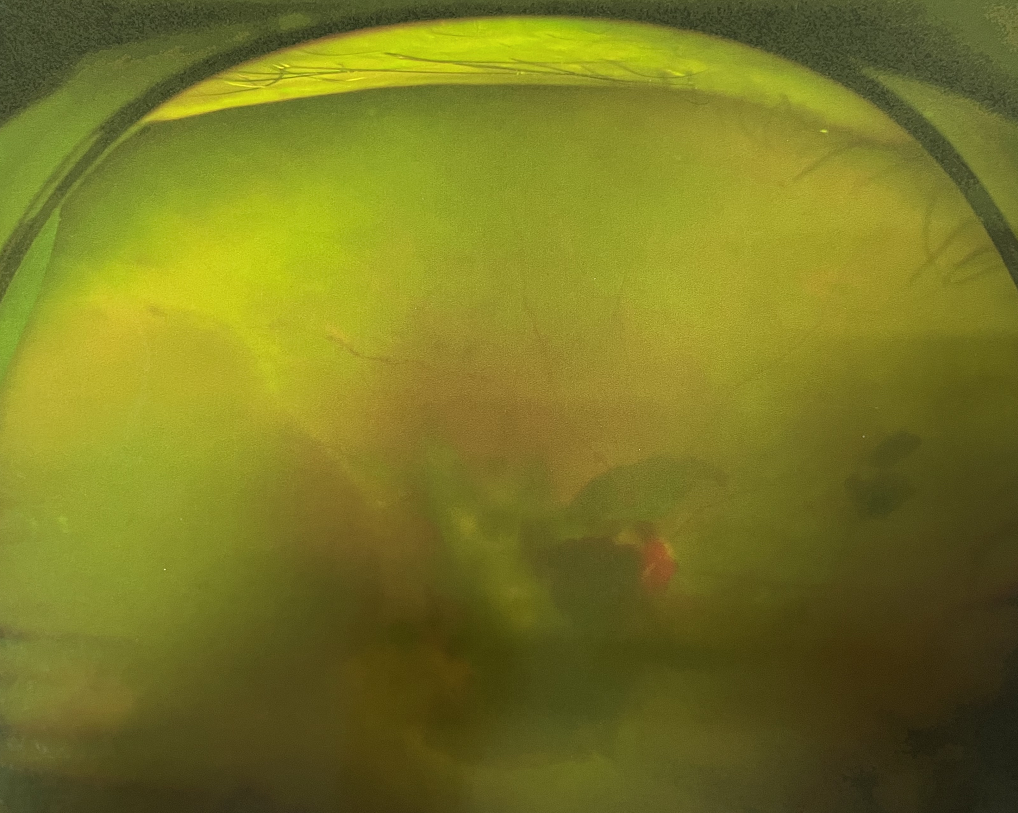

眼底出血不是獨立的眼病,而是由于眼球自己的病變和某些全身疾病的并發(fā)癥導(dǎo)致眼底的視網(wǎng)膜或脈絡(luò)膜出血,如果出血量大就會進(jìn)入到眼球的玻璃體內(nèi),從而影響視力,如果沒有得到恰當(dāng)?shù)闹委熆蓭砀鼑?yán)重的并發(fā)癥造成失明。

眼底出血的患者,如果出血量少,而且在視網(wǎng)膜周邊部可能沒有明顯癥狀,患者僅感到眼前有黑影浮動;如出血量多,將嚴(yán)重影響視力,甚至完全被黑影所遮擋僅剩光感;如出血位于視網(wǎng)膜的黃斑區(qū),患者視野中心區(qū)被暗影遮擋,周邊尚有部分視力。

先是散瞳檢查眼底,可以明確眼底出血的性質(zhì),出血部位和出血量有多少。眼B超檢查,對于眼底出血量特別多,無法看清眼底的患者,就需要進(jìn)行眼部B超檢查,以了解出血量,出血部位、有無合并視網(wǎng)膜脫離;還可以明確是否患有視網(wǎng)膜或脈絡(luò)膜的腫瘤。